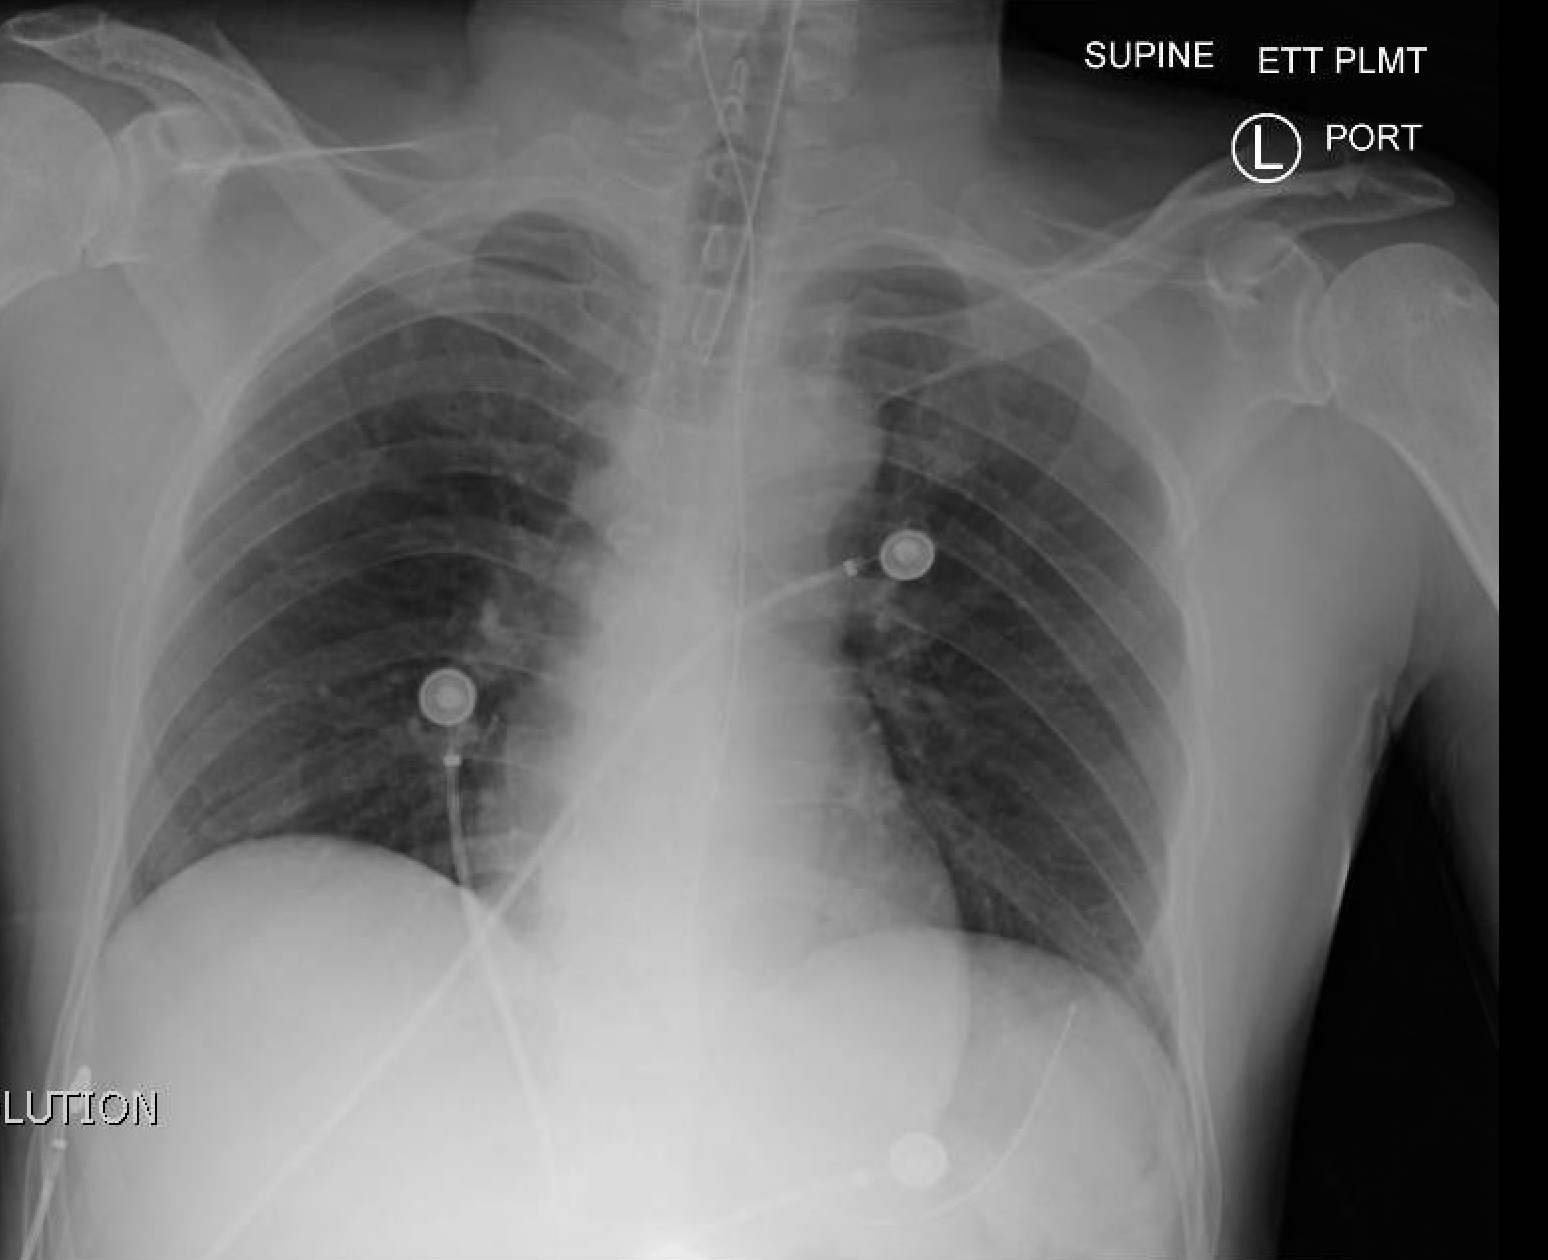

A 5-year-old male with a history of asthma presents with a three-days of cough, wheeze and worsening shortness of breath. The team must recognize severe asthma and initiate usual asthma treatment, but the child does not respond to these basic treatments and continues to worsen. The team should escalate management – epinephrine, magnesium, ketamine. The patient continues to tire and requires intubation. Post-intubation, the team must optimize ventilator settings/paralyze/bear hug. If not treated aggressively, the patient will become hypoxic and bradycardic, potentially leading to arrest.